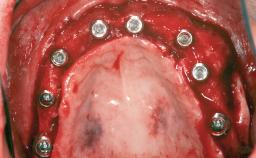

Le Fort I Interpositional Graft and Mandibular Sandwich Osteotomy for Maxillofacial Rehabilitation after Severe Periodontitis

A 47-year-old woman who had suffered from aggressive periodontitis requiring a number of periodontal interventions over more than 10 years was referred by her general dental practitioner and periodontologist for bone augmentation and implant therapy. Her failing dentition had already been scheduled for extraction. The patient expressed a desire for implant-supported fixed restorations and esthetic improvement of her lower face. She had agreed to consult with a maxillofacial surgeon after the referring dentist had suggested bone augmentation. An initial examination by the maxillofacial surgeon revealed mobility of all residual teeth in a patient who was very unhappy with the function of her removable partial dentures. Due to periodontally migrated flaring teeth and loss of occlusal support, the vertical dimension of occlusion was dramatically reduced. The patient was displeased with her lower face because of deepened nasolabial, commissural, and supramental folds.

# of Implants 14

Type of Implants Two-Piece

Prosthesis Type FDP

Defining Characteristics Fully edentulous upper jaw to be rehabilitated with four or more implants

Modality Fixed hybrid bridge on 5+ implants